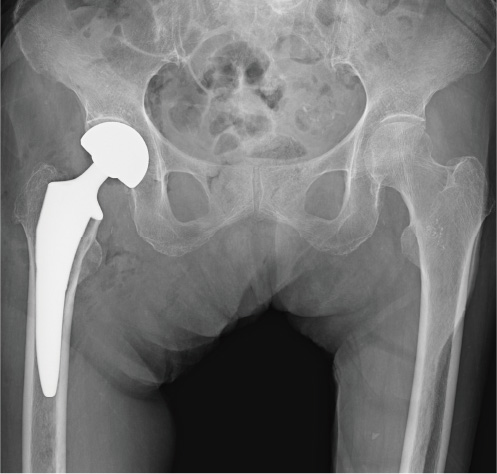

ずれがある(転位型)大腿骨頚部骨折は骨がつきにくく、骨接合術をおこなっても骨癒合が得られず再手術になる確率が高いため、最初から折れた大腿骨頭を人工物に変える手術(人工骨頭置換術)を施行します(図2)。術後早期から 除痛効果が得られ、比較的歩行能力を回復させやすい骨折だと思います。術後合併症として、感染(2~7%)、脱臼(1~5%)などがあります。大腿骨頚部骨折の1年以内の死亡率は10%前後と報告されています。